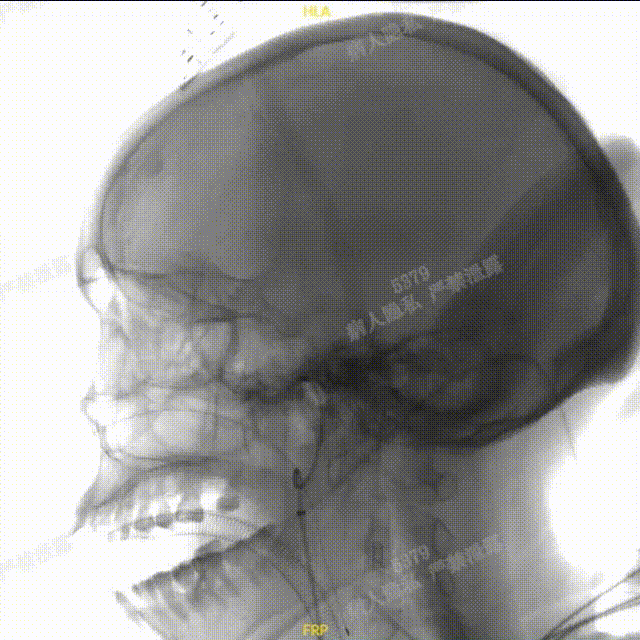

术中DSA造影:右侧颈内动脉工作角度及3D造影,显示右侧颈内动脉海绵窦段动脉瘤。

术中DSA造影:左侧颈总动脉3D造影及左侧椎动脉正位造影。